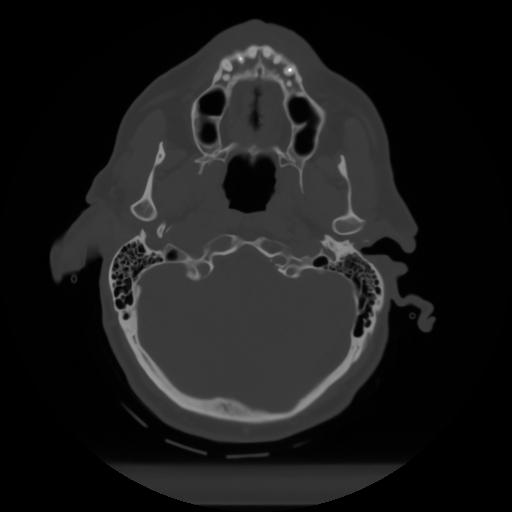

10 P.BLANDAS,,Axial,2.0,P.BLANDAS,,